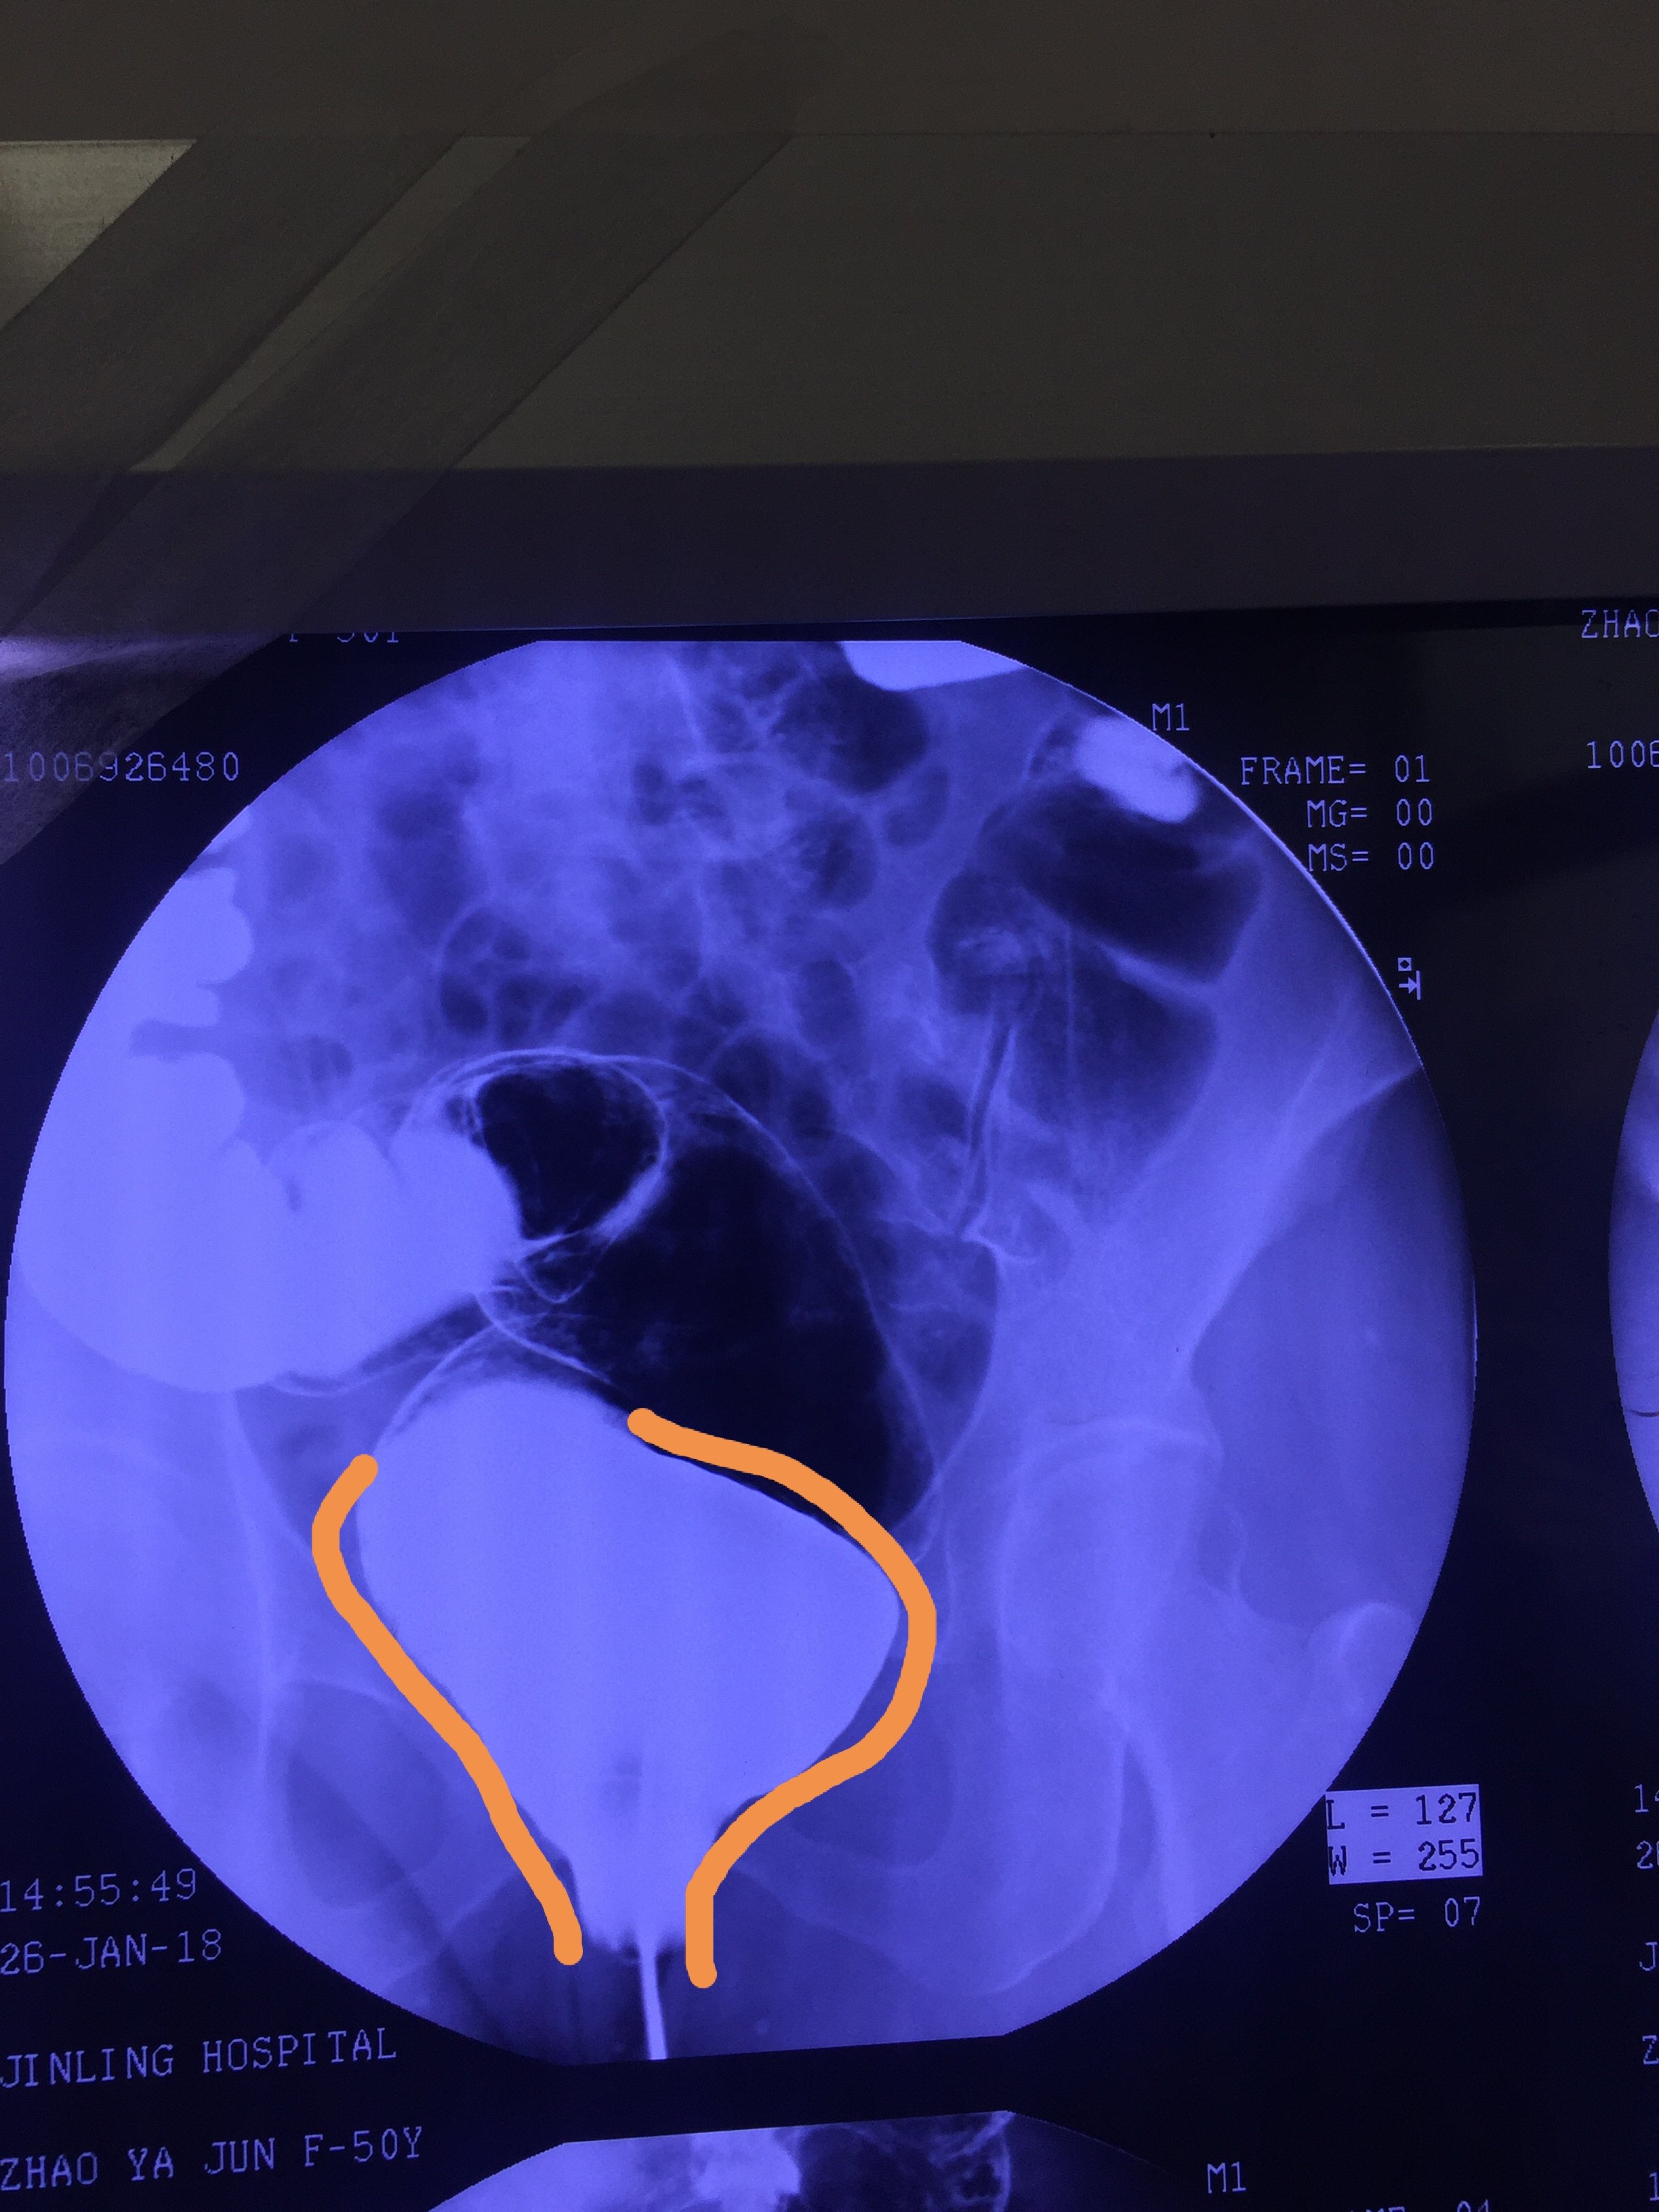

影像学提示肠管广泛扩张,在直乙交界处肠管突然变细,局部肠壁不规则